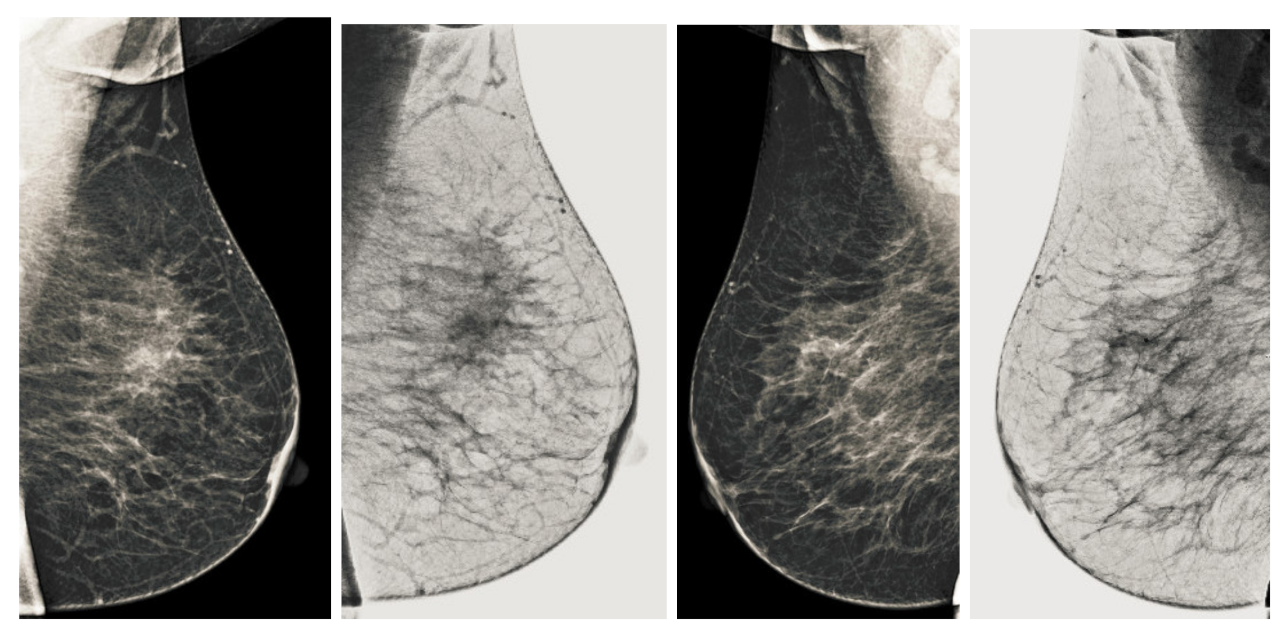

Figure 9.

Analysis of CC view of BI-RADS-2 mammogram images.

Figure 10.

Analysis of MLO view of BI-RADS-2 mammogram images.

We also measured the PSNR, the image contrast, and the EME of each category of databases, as we analyzed the image in terms of visual observation. The Table 3 shows the performance of our proposed image enhancement method. It can be seen from the Table 3 that our proposed method improved PSNR, contrast, and EME, and this also shows that our method can work on every category of BI-RADS. Because many techniques do not work on higher grade BI-RADS due to the complexity and the images are not of good quality. We obtained an average improvement in PSNR, contrast, and EME in the Table 4. For more observations, we analyzed the visual image of each category and we analyzed the CC and MLO of each category as shown in the Figure 7, Figure 8, Figure 9, Figure 10, Figure 11, Figure 12, Figure 13, Figure 14, Figure 15 and Figure 16. From the figures, every detail of image of every category can be observed, leading to better segmentation of the abnormal region. This image enhancement technique can be used as preprocessing steps for the detection of breast cancer. It is a very fast processing algorithm and it takes on 21.13 s. It gives opportunity to medical experts to analyze the mammogram images very quickly to propose the timely treatment.